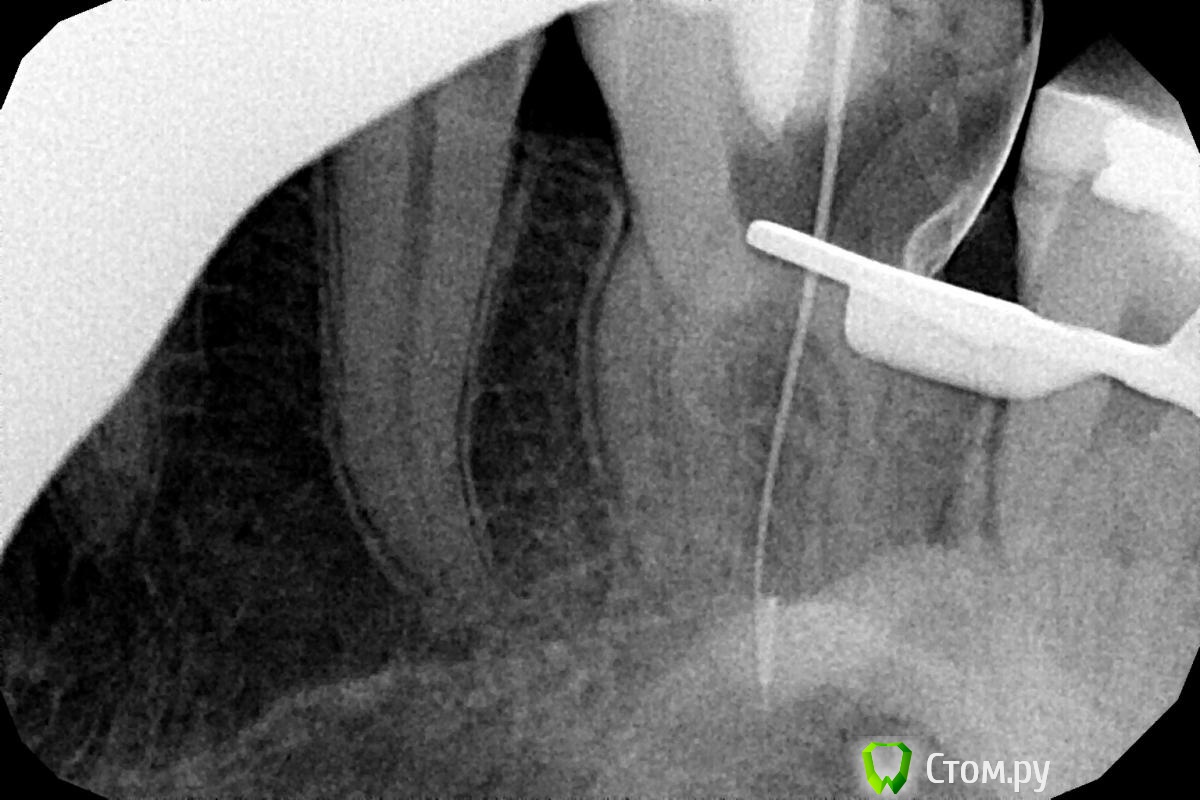

вдгиф Опубликовано 12 января, 2014 Поделиться Опубликовано 12 января, 2014 (изменено) Добрый день, прошу помощи у врачей.Посоветуйте что делать- пытаться ли извлечь инструмент и каковы прогнозы без этой рисковой процедуры. Болел зуб- на приеме у врачас-стоматолога(длился 2 часа) депульпировали зуб.СО СЛОВ ВРАЧА: "Инструмент(профайл 40-06) был сломан на финальной стадии обработки корневых каналов. Обломок инструмента зафиксирован в апикальной трети части корневого канала, поэтому недоступен для обзора в микроскоп. Извлечь его с помощью иглы от шприца(системы) http://rosmicro.ru/?p=2111 невозможно. в настоящий момент в корневых каналах 16 зуба находится гидроокись кальция, замешанная на дистиллированной воде. Зуб закрыт временной пломбой."2 дня была температура(возможно орз- не факт что от зуба). Зубвроде не болит, но дискомфорт какой то есть при жевании.Смущает инфекция возле корня и возможность обойти обломок. Всем откликнувшимся- заранее спасибо! Изменено 12 января, 2014 пользователем вдгиф Ссылка на комментарий

Stomart Опубликовано 12 января, 2014 Поделиться Опубликовано 12 января, 2014 Если был пульпит, то инфекции возле корня нет. Если нет возможности извлечь инструмент, то обойти и запломбировать (на втором снимке он вроде как обойден). А еще поискать четвертый канал. 2 Ссылка на комментарий

Kolchanov Опубликовано 12 января, 2014 Поделиться Опубликовано 12 января, 2014 Судя по описанию и снимку, лечение проводилось как надо. К сожалению, инструменты иногда ломаются. Но, учитывая то, что зуб был витальный (пульпит), инструмент сломан в конце обработки, была изоляция зуба от полости рта, то можно рассчитывать на высокий успех лечения даже если инструмент не будет извлечен. Запломбируйте каналы у того же доктора и восстановите его рекомендованным способом (коронка, скорее всего). Все будет в порядке. Ссылка на комментарий

DmitrySH Опубликовано 12 января, 2014 Поделиться Опубликовано 12 января, 2014 Все должно нормально обойтись, не волнуйтесь. П.С. В небных каналах инструменты обычно ломаются не по вине врача, это судьба. 1 Ссылка на комментарий